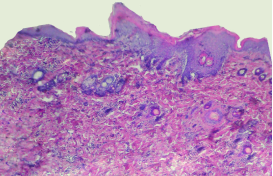

Гистологические процессы